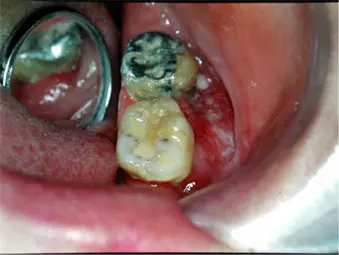

- 虫歯のある方(鋭端(とがった部分)の刺激と関係アリ?)

- 入れ歯や差し歯のある方(不良な入れ歯や差し歯の刺激と関係アリ?)